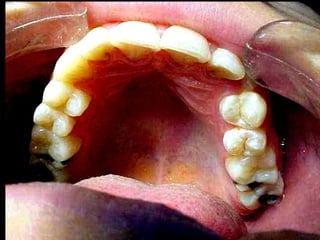

Pulpitis Crónica Hiperplásica

Imagen clínica. Observe en la diapositiva un primer molar inferior

de un niño de 12 años cuya cara oclusal tiene una cavidad de caries;

toda ella ocupada por una gran masa carnosa rosada correspondiente

a un pólipo pulpar que protruye de la pulpa.